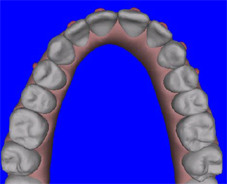

| תמונת השיניים העליונות בסיום הטפול | מודל סיום הטפול, כפי שתוכנן מראש (אינביזאלין) |